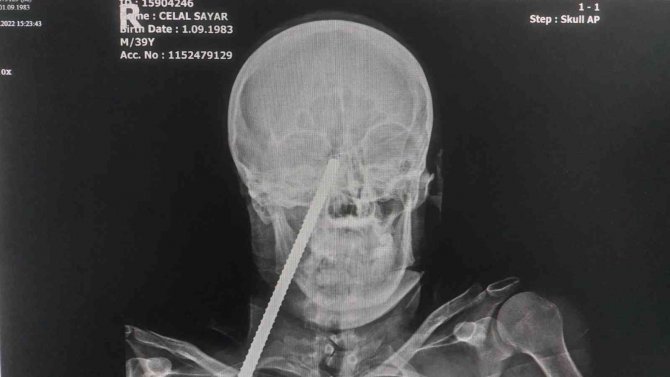

Yüzüne Saplanan Demirle Hastaneye Kaldırıldı

Giresun'da çalıştığı inşaatta düşerek yüzüne demir saplanan işçinin sevk edildiği Samsun'daki hastanede ameliyatla yüzündeki demir çıkartıldı.

Edinilen bilgiye göre, Giresun'da çalıştığı inşaatta demirin üzerine düşen Celal Sayar'ın (39) yüzüne inşaat demiri saplandı. Yüzünde demir saplı halde Giresun'daki hastaneye kaldırılan Sayar, ilk müdahalesinin ardından demirin yüzünden çıkartılması için Samsun'a sevk edildi. Celal Sayar, Samsun Eğitim ve Araştırma Hastanesinde ameliyata alındı. Yüzündeki demir çıkartılan Sayar, daha sonra hastanenin yoğun bakım servisinde tedavi altına alındı.